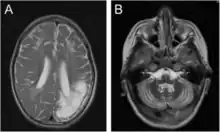

Encéphalomalacie chez un garçon de 7 ans : en imagerie par résonance magnétique (àa gauche) et en tomodensitométrie (à droite)